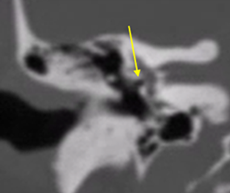

Tomografia

La evaluación mediante tomografía es fundamental para identificar los focos otoscleróticos, principalmente en la ventana oval a nivel de la fissula antefenestran, la cual es un surco que se localiza entre la ventana oval y el proceso cocleariforme. En la fase otospongiótica o activa de la otosclerosis, se pueden observar áreas hipodensas en el hueso, mientras que en la fase inactiva otosclerótica, se observara hueso compacto que puede afectar progresivamente la platina del estribo, provocando la fijación de este.

El grosor normal de la ventana oval se establece en 1.64 mm; valores superiores a 3 mm son considerados compatibles con otosclerosis. En un bajo porcentaje, alrededor del 10%, se presenta un subtipo retrofenestral, que afecta la cápsula ótica y puede resultar en desmineralización, lo que se clasifica como "otosclerosis muy avanzada", según lo definido por House y Sheehy.93 A continuación, se detallan las diferentes clasificaciones relacionadas con esta patología (Tabla 2 y 3).

Tamaño del nicho de la ventana oval: Valores de 1,4 mm se toma como límite inferior de la normalidad. Valores menores se asociaban con un riesgo mayor de tener dificultades técnicas durante la cirugía del estribo. Debe descartarse una otosclerosis obliterativa (Fig. 4-5). |

Figura 4. Vista de la ventana oval en un corte coronal del oído medio |

Figura 5. Ventana oval obliterativa de oído derecho en un corte coronal de oído medio |